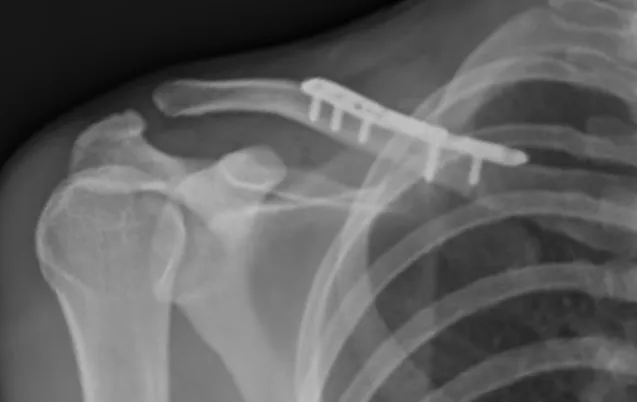

Il consiste en la réalisation d'une ostéosynthèse (repositionnement et fixation des fragments osseux), le plus souvent par une plaque vissée. L'intervention est réalisée sous anesthésie générale, parfois associée à une anesthésie loco-régionale. Un contrôle radiographique per-opératoire permet au chirurgien d'avoir un contrôle parfait du positionnement du matériel.

Après l'intervention, le bras est immobilisé dans une attelle coude au corps pendant 4 à 6 semaines. La rééducation débute après 4 semaines chez un kinésithérapeute de ville.